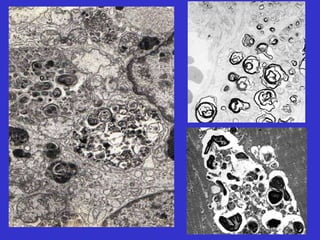

Sistemas sub-celulares vulneráveis

Membranas celulares (manutenção da integridade)

Mitocôndria (respiração aeróbica e produção de ATP)

Síntese protéica (proteínas enzimáticas e estruturais)

Integridade do genoma

Lesão e morte celular

● Depleção de ATP.

● Oxigênio e radicais livres derivados.

● Aumento de Cálcio intracelular e perda de

homeostasia de cálcio.

● Alterações na permeabilidade da membrana.